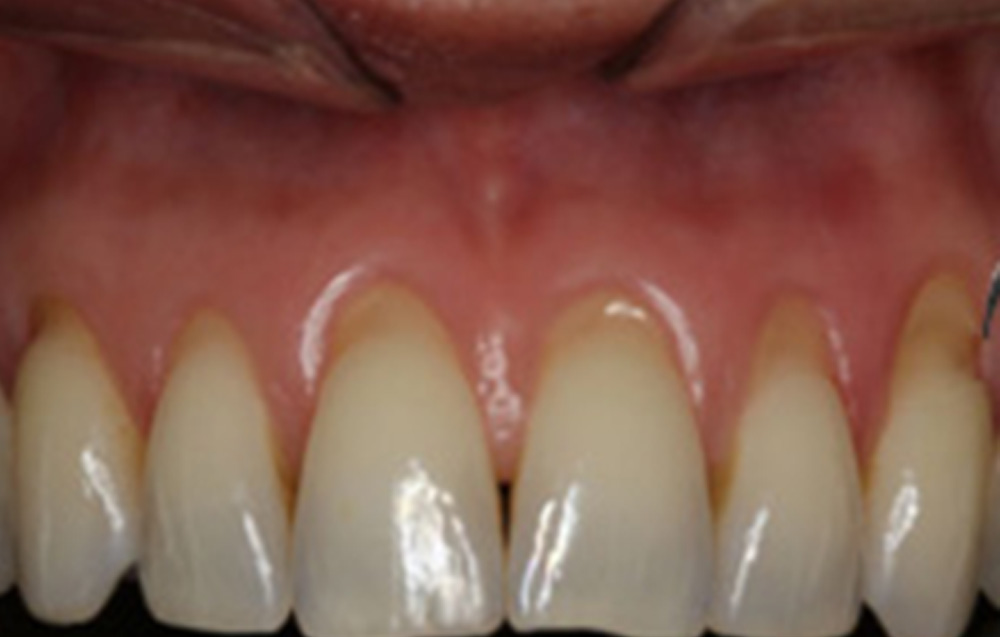

When your gums recede, the roots of the teeth may become visible. This can increase the risk of cavities in the root of the tooth.

Pinhole® Surgical Technique (PST™) is a specialized procedure for correcting gum recession without incisions, sutures, or transplants. This is achieved by making small holes in the gums near the affected areas.

Dr. Ghayoumi can gently loosen and insert the gums to cover the exposed tooth roots and restore a healthier gum line through these holes.